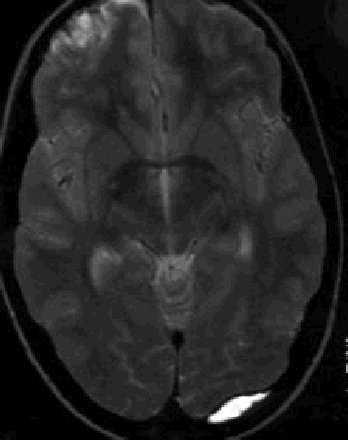

Hematoma epidural. Colección de sangre venosa (occipital, por afectación de senos) o arterial (parietal, por afectación de la arteria meníngea media) en el espacio situado entre la duramadre y la tabla interna del cráneo. Su prevalencia es del 1 al 5% de los TCE en niños. Se presenta predominantemente en menores de 2 años (50%). En la neuroimagen (fig. 5) se observa en forma de lesión extensa extraaxial hiperdensa de contorno convexo hacia la línea media (lenticular o biconvexa). Clínicamente cursan con alteración de la conciencia, focalidad neurológica y signos de hipertensión intracraneal. Una pupila dilatada fija, ipsolateral, está presente en el 90% de los casos. A diferencia de lo que sucede en los adultos, es excepcional la existencia de una fase lúcida. Se añade fractura craneal asociada en el 40% de los niños, en comparación con el 80 al 90% de los adultos. La actitud a adoptar pasa por el tratamiento neuroquirúrgico urgente y el ingreso en UCIP. Rara vez se optará por un tratamiento más conservador.

Fig. 5. Resonancia nuclear magnética (potenciada en T2). Hematoma epidural occipital. Contusión hemorrágica frontal contralateral.